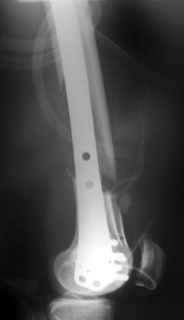

Both options are good, my concern with LISS:

1. In this particular case 2 things may happen:

A. Knee stiffness

B. If the gap left as wide as it is on the post op x ray it may led to Non union.

Solution:

For A.: use plate with better proximity to the bone, to free up the IT band (may not be LISS, Zimmer, and I think now Smith and Nephew lately, make very good distal femur plates

For B: compress the fragments (shorten the femur), 1 cm will not affect extremity/ gait in any substantial way.

Great case.